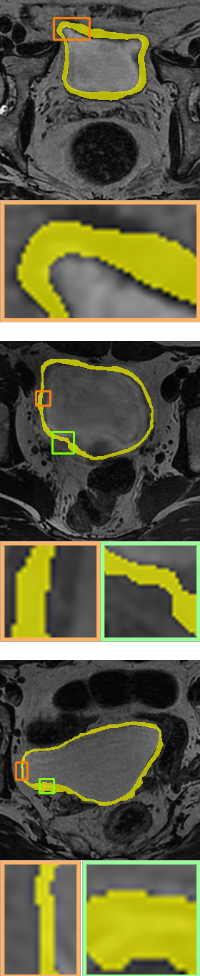

In this section, we test the energy without width information Eq. 11, denoted PH, and the width-aware topological energy Eq. 12, denoted WT, in the data-driven segmentation models.

Magnetic resonance imaging-based segmentation of the inner and outer bladder wall dataset [isicdm] is from the Third International Symposium on Image Computing and Digital Medicine, which is called the ISICDM dataset. We select images from the dataset that are single-connected and contain one genus and divide them subsequently into training (480), validation (80) and test (120) sets. The size of each image in the dataset is 512 × 512, and the goal is to achieve accurate segmentation of the inner and outer boundaries of the bladder.

Ground-truth

Without-topo

PH[ph]

Proposed WT

We compare the results of no topological constraints (without-topo), topological constraints without width (PH), and width-aware topological constraints (WT) applied to a number of data-driven models for relevant applications. As can be seen in Table 3, our proposed method (rows with gray background) shows superior performance. Specifically, the improvements in volumetric demonstrate that our method has more accurate result in a pixel-level sense, while the improvements on topology-based metrics demonstrate that WT energy has an overall more precise prediction and topological similarity. For boundary-based indicators, WT performs better compared to PH in most cases due to the width information. The corresponding visualization is given in Fig. 10 and Fig. 11. From the visualization results, it can be seen that in data-driven image segmentation models, no topological constraints will produce obvious topological errors, even if its segmentation results have high accuracy. When constraining topological consistency using persistent homology methods, it may be possible to connect very thin lines to ensure connectivity or a consistent number of holes. We improve the PH method by smoothing the critical points in there structuring elements neighborhood, which can preserve the width information while constraining the topological properties to be consistent.